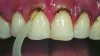

A 55-year-old woman presented with root decay along the left lateral incisor (tooth No. 10) and canine (tooth No. 11) (Figure 1). It was proposed that invisible Class V restorations be placed using an MMID procedure. There are several keys to attaining a successful invisible Class V restoration. Proper understanding of composite resin shade selection, preparation design, and sequence of composite resin layering are important to achieve an ideal blending of the composite resin to the existing tooth. Correct finishing and polishing technique is equally essential in obtaining a seamless esthetic restoration.3,11

Shade selection is always completed before initiating treatment; this is important to develop the proper shade-layering sequence. Composite shades were placed directly on the tooth and shades that matched the areas of the tooth being restored were chosen (Figure 2). To achieve an invisible Class V restoration, a more complex layering process is needed to blend the composite resin.